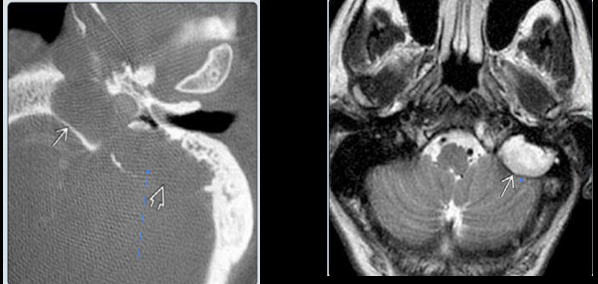

Imagen en colesteatoma

Masa que destruye el hueso

Definición colesteatoma

Neoplasia tej epidérmico que crece en interior de conducto auditivo

Beningno - comportamiento maligno pq destruye hueso